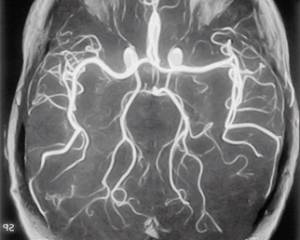

- Дисциркуляторная (сосудистая) энцефалопатия.

- Подкорковая атеросклеротическая энцефалопатия, характеризующаяся атрофией белого вещества головного мозга и имеющая различные причины.

В частности, дисциркуляторная энцефалопатия проявляется головокружением, проблемами с памятью и речью, а также быстрой утомляемостью. Диагноз устанавливается на основе наличия этих симптомов в течение длительного времени (более 6 месяцев).

Для

подкорковой

атеросклеротической энцефалопатии характерны потеря памяти и снижение интеллектуальных способностей. Обычно болезнь развивается в возрасте 55-65 лет и сопровождается колебаниями артериального давления. При прогрессировании заболевания наблюдается ухудшение памяти и координации движений, что делает невозможным самостоятельное существование пациента.